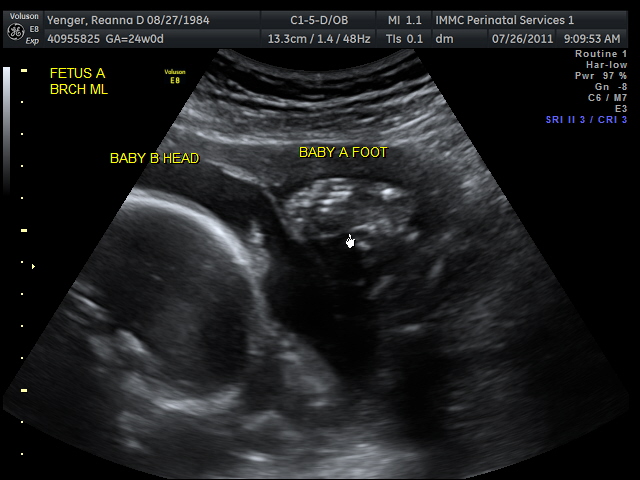

Here are a few ultrasound pictures from today:

This is Ainsley kicking Benson in the head: